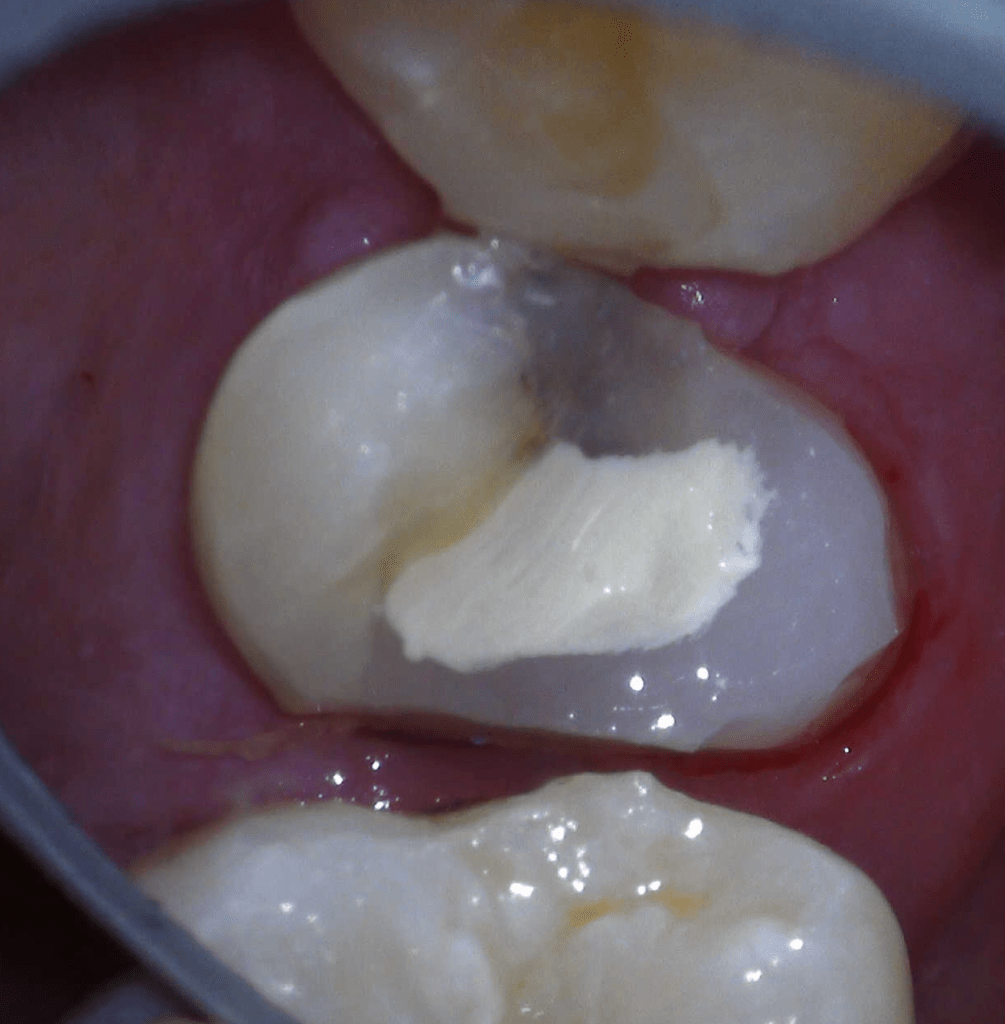

Pulpotomía biodentine + reco preendio